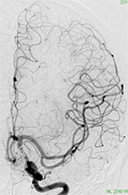

くも膜下出血の原因となる脳動脈瘤(のうどうみゃくりゅう)の外科治療

63歳女性、左眼視力低下で発症

<画像所見>

左眼の奥に大きな動脈瘤認める。

(→動脈瘤)

<手術中の脳血管撮影画像>

瘤(こぶ)は消失